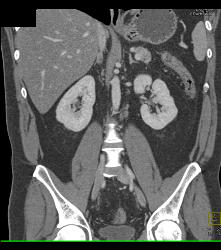

Diagnosis

Colitis